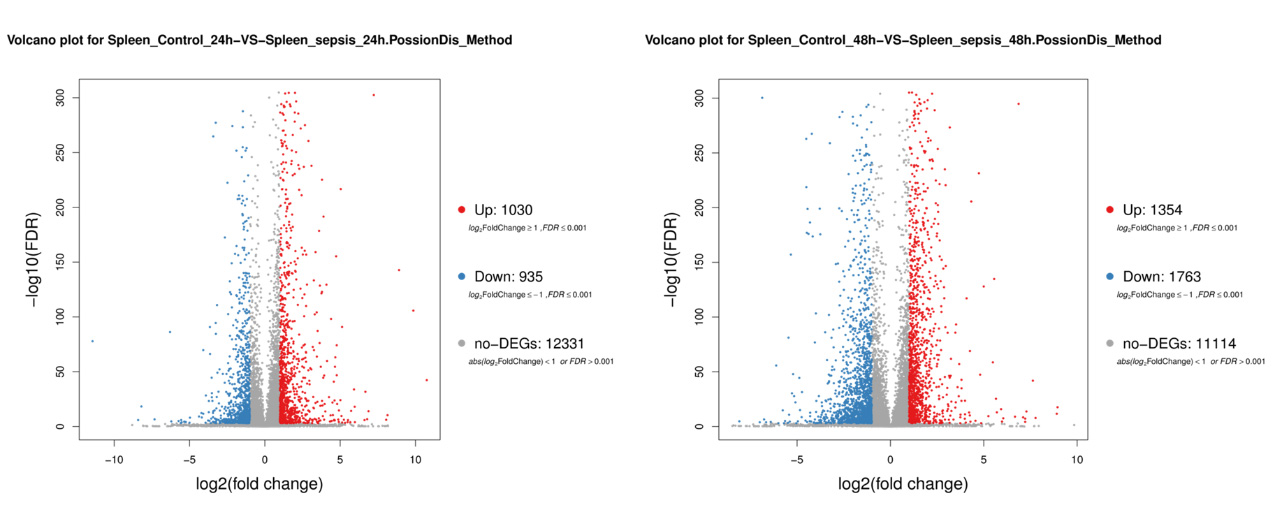

2 结果48 h各组病理结果,对照组脾组织结构正常(见图 1A )。脓毒症组脾组织见白髓结构破坏,红白髓交界模糊,多量组织细胞浸润,红髓充血(见图 1B)。差异mRNA的Volcano-plot分布图(见图 2)。相比于对照组,24 h时脓毒症组脾组织mRNA表达上调的有1 030个,下调的有935个[5];48 h组表达上调的有1 354个,下调的有1 763个。差异mRNA的聚类情况(见图 3)。GO功能分类结果(见图 4)。脓毒症大鼠脾组织部分通路相关基因表达情况(见图 5、6):脓毒症大鼠24 h,48 h脾组织关于细胞因子及其受体相互作用通路相关基因的分布图(见图 7,图 8)。脓毒症大鼠24 h,48 h脾组织关于细胞凋亡相关通路的基因分布图(见图 9,图 10)。

| 注:DEG:差异表达基因;:X轴:log2转换后的差异倍数值,Y轴:-log10转换后的显著性值。红色:上调的DEG,蓝色:下调的DEG,灰色:非DEG 图 2 DEG的Volcano-plot分布图 |

早期过度炎症反应、晚期免疫抑制系脓毒症的重要机制之一[6-7]。脾脏为人体免疫器官,在血源性抗原出现时,负责启动免疫反应[9]。脓毒症时SIRS反应可引起脾功能障碍[10]。本研究发现脓毒症48 h大鼠脾组织白髓结构破坏,红白髓交界模糊,其结构改变可能影响其免疫功能。既往对脓毒症大鼠24 h采用基因芯片分析发现部分基因表达异常[11]。若能进一步研究其早晚期的相关基因表达变化也许对脓毒症脾功能障碍有进一步的诠释。本研究采用RNA-seq技术对脓毒症大鼠早晚期脾组织行mRNA检测,是既往研究的深入,发现脓毒症早期组脾组织基因上下调数远少于晚期组,如脓毒症24 h组脾组织mRNA上调数1 030个,下调数935个,而48 h组mRNA上调数1 354个,下调数1 763个,差异明显(见图 2),符合疾病的发展过程。从图 3看,脓毒症24 h、48 h部分区域从红色趋于变浅甚至变蓝,浅蓝趋于蓝色,直观的反应脓毒症时脾脏基因表达量变化情况。从GO功能分类结果(图 4)得知,cellular processes、Environmental informationProcessing、Genetic Information Processing、Human Diseases、Metabolism、Organismal Systems相关功能基因随时间发展出现差异表达数为上升趋势。进而我们对其分析发现,脓毒症早晚期脾mRNA出现变化主要涉及细胞因子与其受体相互作用、IL-17、T细胞受体、TH1、TH2细胞分化、TNF、Toll受体、凋亡等相关信号通路。研究显示,脓毒症晚期免疫抑制可能是脓毒症患者死亡的主要原因,免疫治疗可能是未来一大趋势[12-15]。本文拟从炎症反应与细胞凋亡相关通路来阐述脓毒症脾功能障碍的相关机制。